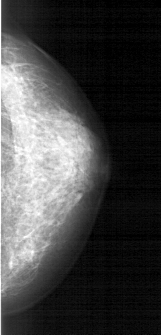

A_1609_1.LEFT_MLO

LEFT_CC LINES 4006 PIXELS_PER_LINE 1861 BITS_PER_PIXEL 12 RESOLUTION 43.5 OVERLAY

LEFT_MLO LINES 5191 PIXELS_PER_LINE 2056 BITS_PER_PIXEL 12 RESOLUTION 43.5 OVERLAY